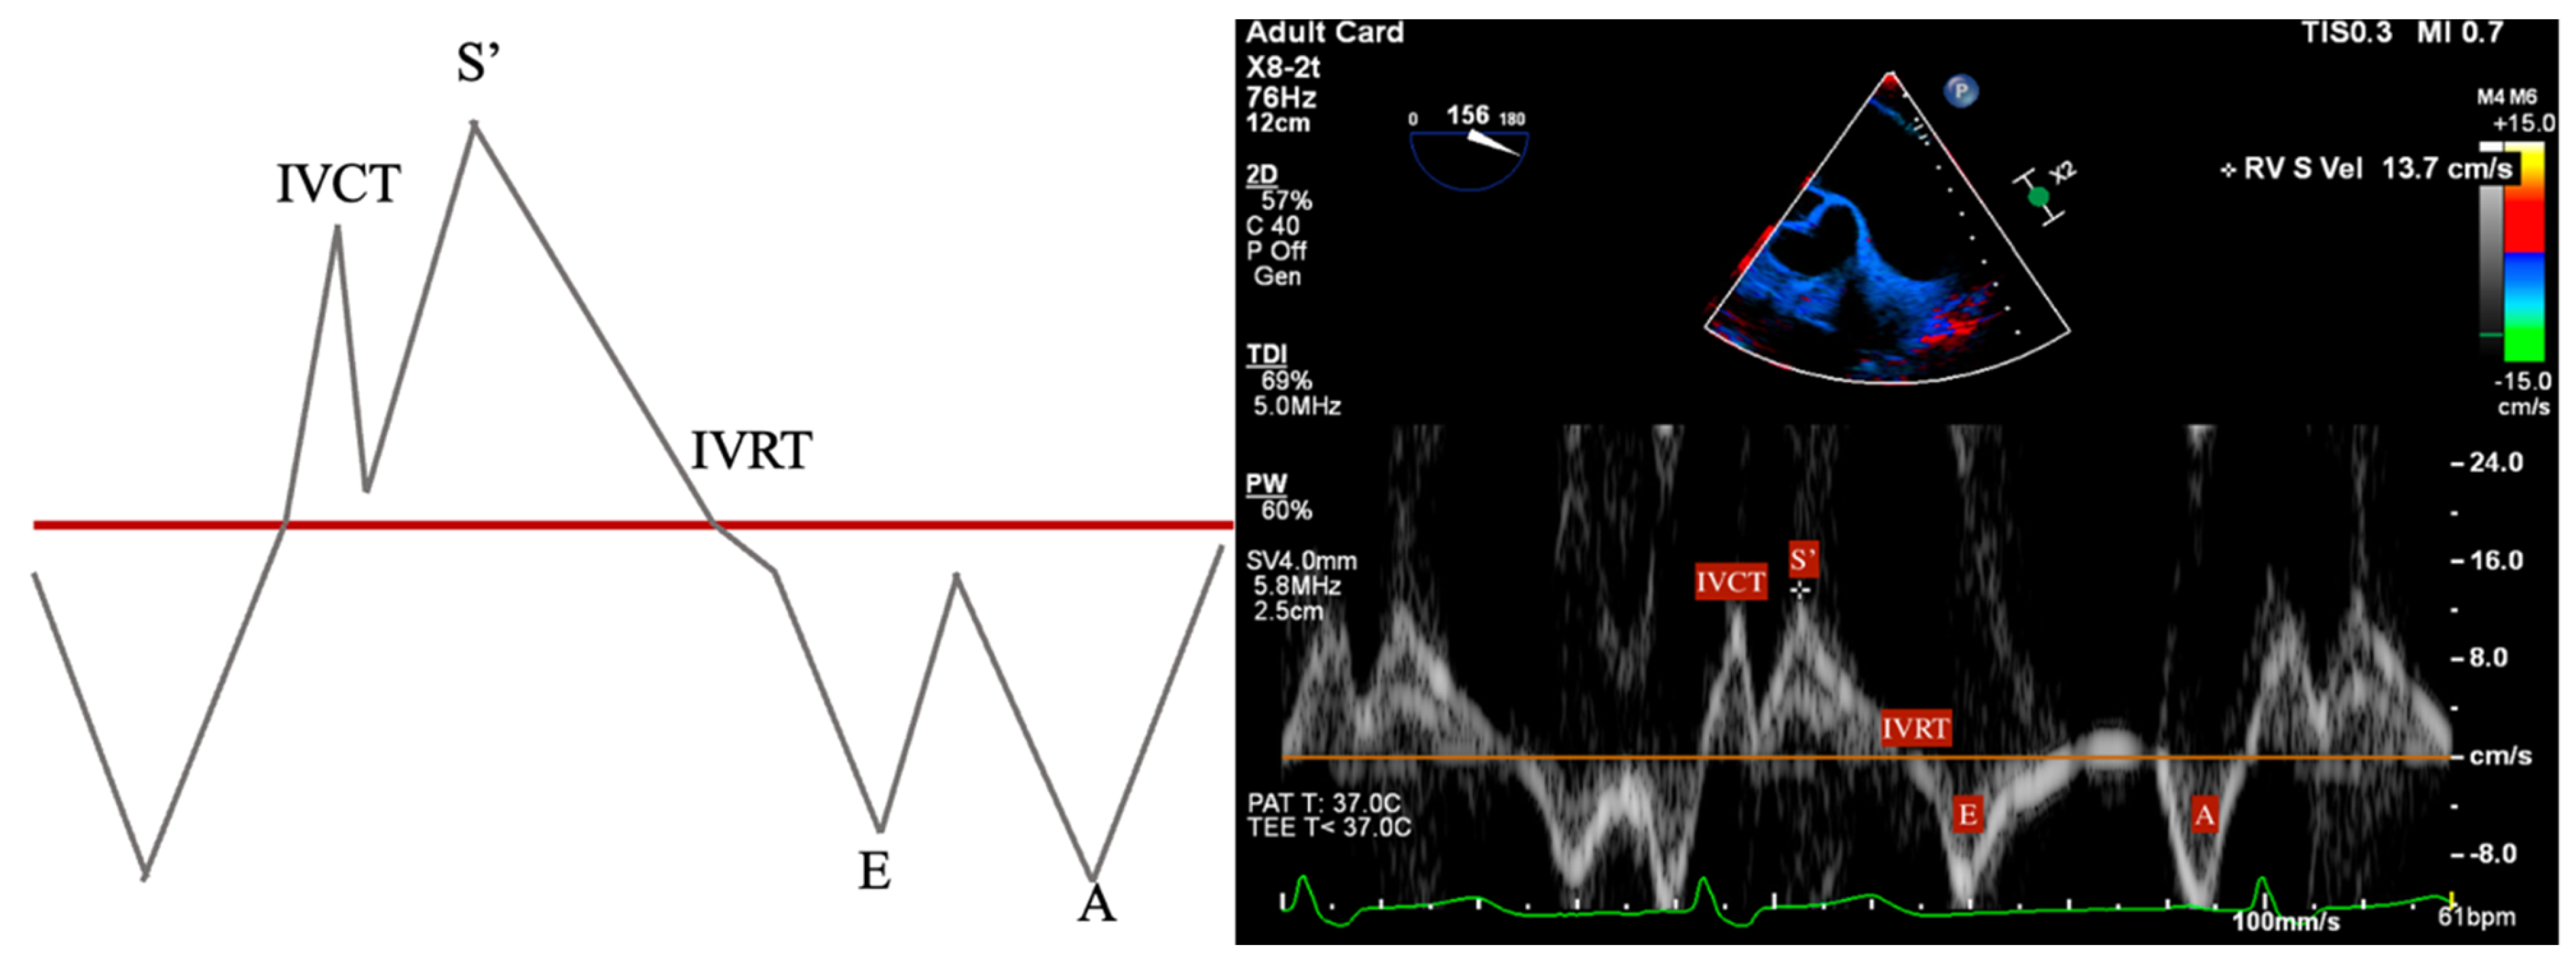

- S’: Measured from a non-standard TEE view. In the Deep Transgastric long axis (DTG-LAX) view, omniplane to 120–150° and turn right. The RV and lateral tricuspid annulus will be centered on the screen. Tissue Doppler Imaging (TDI) is then used to measure the systolic velocity of the lateral tricuspid valve annulus (S’) with >10 cm/s considered normal [79] (Figure 4 and Figure 5).